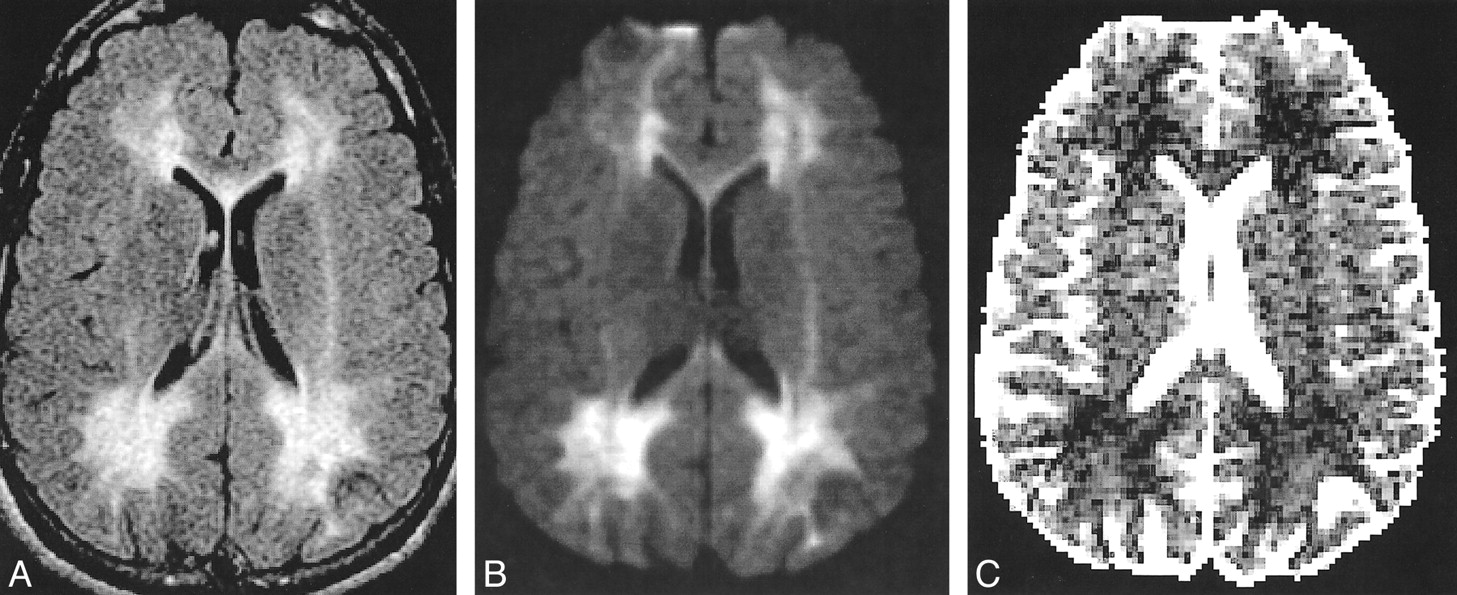

Diffusion-Weighted Imaging of White Matter Abnormalities in Patients

Now, let’s turn our attention to diffusion-weighted imaging (DWI) and the fascinating insights it provides. DWI is a technique used in radiology to examine the movement of water molecules within tissues. It’s particularly useful in detecting and characterizing white matter abnormalities in patients.

Now, let’s turn our attention to diffusion-weighted imaging (DWI) and the fascinating insights it provides. DWI is a technique used in radiology to examine the movement of water molecules within tissues. It’s particularly useful in detecting and characterizing white matter abnormalities in patients.

White matter abnormalities can occur due to various conditions, including stroke, multiple sclerosis, and traumatic brain injury. DWI allows healthcare professionals to visualize and analyze these abnormalities, providing crucial information for diagnosis, treatment, and monitoring of patients.

By studying the unique patterns and locations of white matter abnormalities revealed by DWI, doctors can gain a better understanding of the underlying causes and tailor treatment plans accordingly. This groundbreaking imaging technique has revolutionized the field of neuroimaging and continues to pave the way for advanced diagnostics and patient care.

www.ajnr.orgphenylketonuria pku diffusion abnormalities existence fabry weighted powerpoint ajnr

www.ajnr.orgphenylketonuria pku diffusion abnormalities existence fabry weighted powerpoint ajnr

Pku phenylketonuria management treatment facts prevention dietary nutrition sravani september posted. Pku phenylketonuria matter fig. Diffusion-weighted imaging of white matter abnormalities in patients